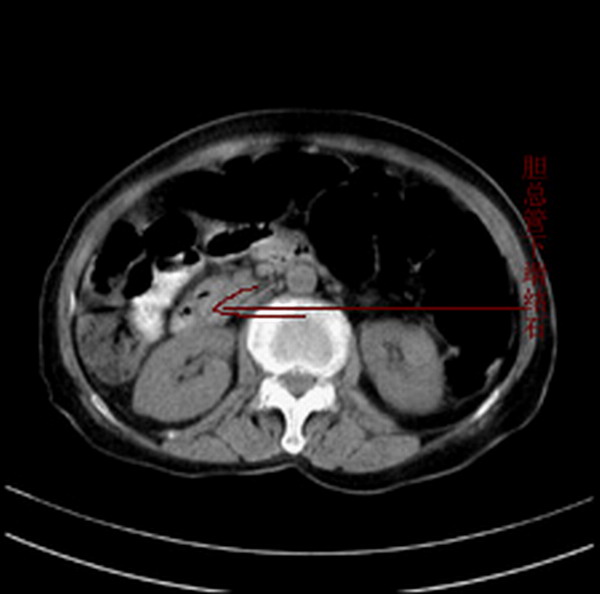

胆总管结石

胆总管多发结石

胆总管多发结石伴肝内外胆管轻度扩张。

胆总管上段,腔内有软组织密度影 ,ct值36-44hu。大家看有没有胆管癌的可能。

典型胆总管多发结石;增强扫描前后ct值是否发生改变是鉴别结石与占位的依据。

典型的胆总管多发结石。在没有增强的情况下,暂不考虑其他。

胆总管多发结石伴肝内外胆管扩张。

胆管没有鼠尾征,还是考虑结石

胆管结石并发胆管炎。

环形结石

胆管癌并结石。